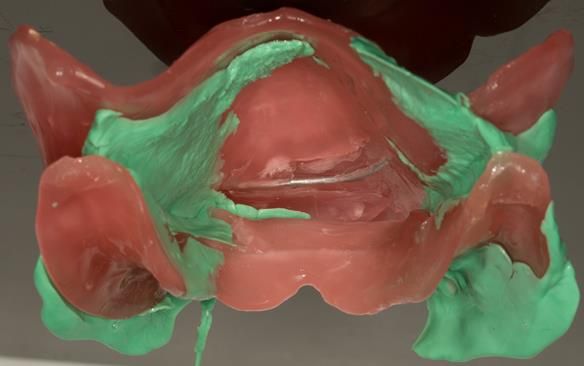

This newsletter describes in step by step detail the transition from acrylic based immediate dentures to metal based definitive dentures.

- Definitive dentures (Mk 2) – complete upper metal reinforced and lower cobalt chromium based partial of hygienic Scandinavian design to be made 9 - 12 months after extractions of all upper teeth and LR5 and LL4

The clinical situation and treatment process is shown in detail below with photographs.